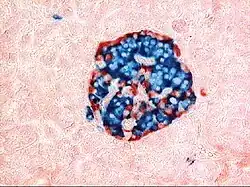

The tissues with an endocrine role within the pancreas exist as clusters of cells called pancreatic islets (also called islets of Langerhans) that are distributed throughout the pancreas.[9] Pancreatic islets contain alpha cells, beta cells, and delta cells, each of which releases a different hormone. These cells have characteristic positions, with alpha cells (secreting glucagon) tending to be situated around the periphery of the islet, and beta cells (secreting insulin) more numerous and found throughout the islet.[9] Enterochromaffin cells are also scattered throughout the islets.[9] Islets are composed of up to 3,000 secretory cells, and contain several small arterioles to receive blood, and venules that allow the hormones secreted by the cells to enter the systemic circulation.[9]

Pancreatic progenitor cells differentiate into endocrine islet cells under the influence of neurogenin-3 and ISL1, but only in the absence of notch receptor signaling. Under the direction of a Pax gene, the endocrine precursor cells differentiate to form alpha and gamma cells. Under the direction of Pax-6, the endocrine precursor cells differentiate to form beta and delta cells.[17] The pancreatic islets form as the endocrine cells migrate from the duct system to form small clusters around capillaries.[9] This occurs around the third month of development,[11] and insulin and glucagon can be detected in the human fetal circulation by the fourth or fifth month of development.[17]

Cells within the pancreas help to maintain blood glucose levels (homeostasis). The cells that do this are located within the pancreatic islets that are present throughout the pancreas. When blood glucose levels are low, alpha cells secrete glucagon, which increases blood glucose levels. When blood glucose levels are high beta cells secrete insulin to decrease glucose in blood. Delta cells in the islet also secrete somatostatin which decreases the release of insulin and glucagon.[9]

The way the tissue of the pancreas has been viewed has also changed. Previously, it was viewed using simple staining methods such as H&E stains. Now, immunohistochemistry can be used to more easily differentiate cell types. This involves visible antibodies to the products of certain cell types, and helps identify with greater ease cell types such as alpha and beta cells.[9]